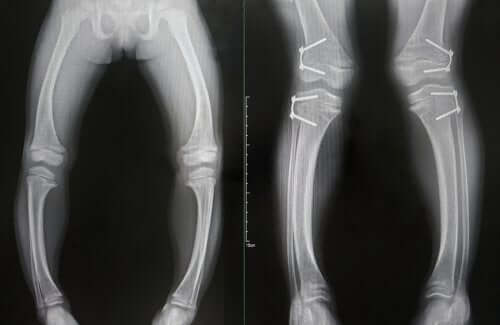

- Deformidades nos ossos, que se tornam moles: o mais comum é que surja um arqueamento dos ossos das pernas. No entanto, o desgaste também pode ocorrer nas extremidades de alguns ossos.

O diagnóstico de raquitismo é baseado na combinação dos resultados dos exames de laboratório e de imagem alterados, juntamente com a presença dos sintomas clínicos típicos que vimos anteriormente.